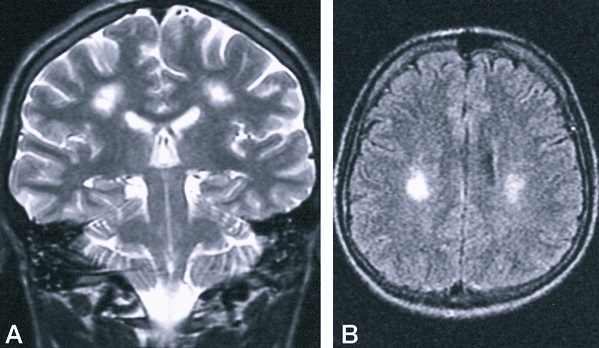

Чтобы выявить очаги глиоза, применяют МРТ. Процедура позволяет определить размер и локализацию очага, его порог. На основе этих данных в комплексе с другими исследованиями, анализами невропатолог может установить точную причину появления очагов поражения, а также предвидеть возможные последствия.

- Томография (КТ, МРТ). Визуально покажет состояние мозга, поможет определить объем и локализацию повреждений. При томографии можно легко выявить заболевания сосудистого генезиса. МРТ фиксирует нарушенный обмен веществ, рубцы, опухоли и т.д. При помощи МРТ можно диагностировать глиоз белого вещества в лобных долях. Другими методами этот процесс не выявить. Именно МРТ позволяет обнаружить перивентрикулярный глиоз, который поражает зоны около желудочков мозга. Также этот метод помогает диагностировать периферические и перифокальные поражения.